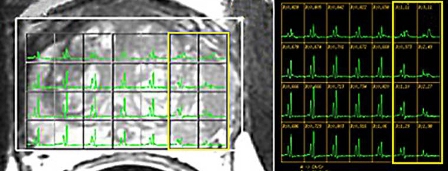

Enter Sadhna Verma (right), MD, of the University of Cincinnati. She’s a radiologist that combines magnetic resonance and 3T spectroscopy to image the body. These images are used to form a diagnosis before the use of invasive measures. Verma’s philosophy is to identify precisely the stage of prostate cancer present, which can make a difference in the proper medical response. "Men have several choices when it comes to prostate cancer treatment. Accuracy of staging is critical for choosing the approach that is right for each individual.” In Wentzel’s case, Verma was able to immediately locate a mass in the prostate, which was examined and confirmed to be the result of Gleason grade 7 prostate cancer. The mass was removed successfully in August of this year.

(images courtesy of the University of Cincinnati)